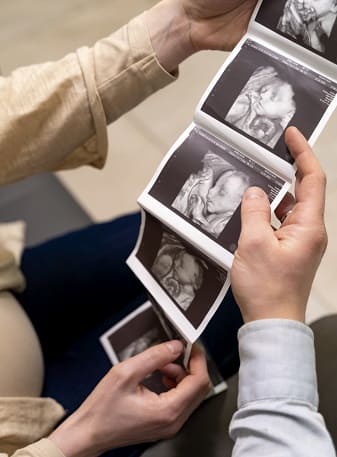

Realizamos ultrasonidos generales y especializados como Doppler, que permiten evaluar el flujo sanguíneo en diversas áreas del cuerpo.